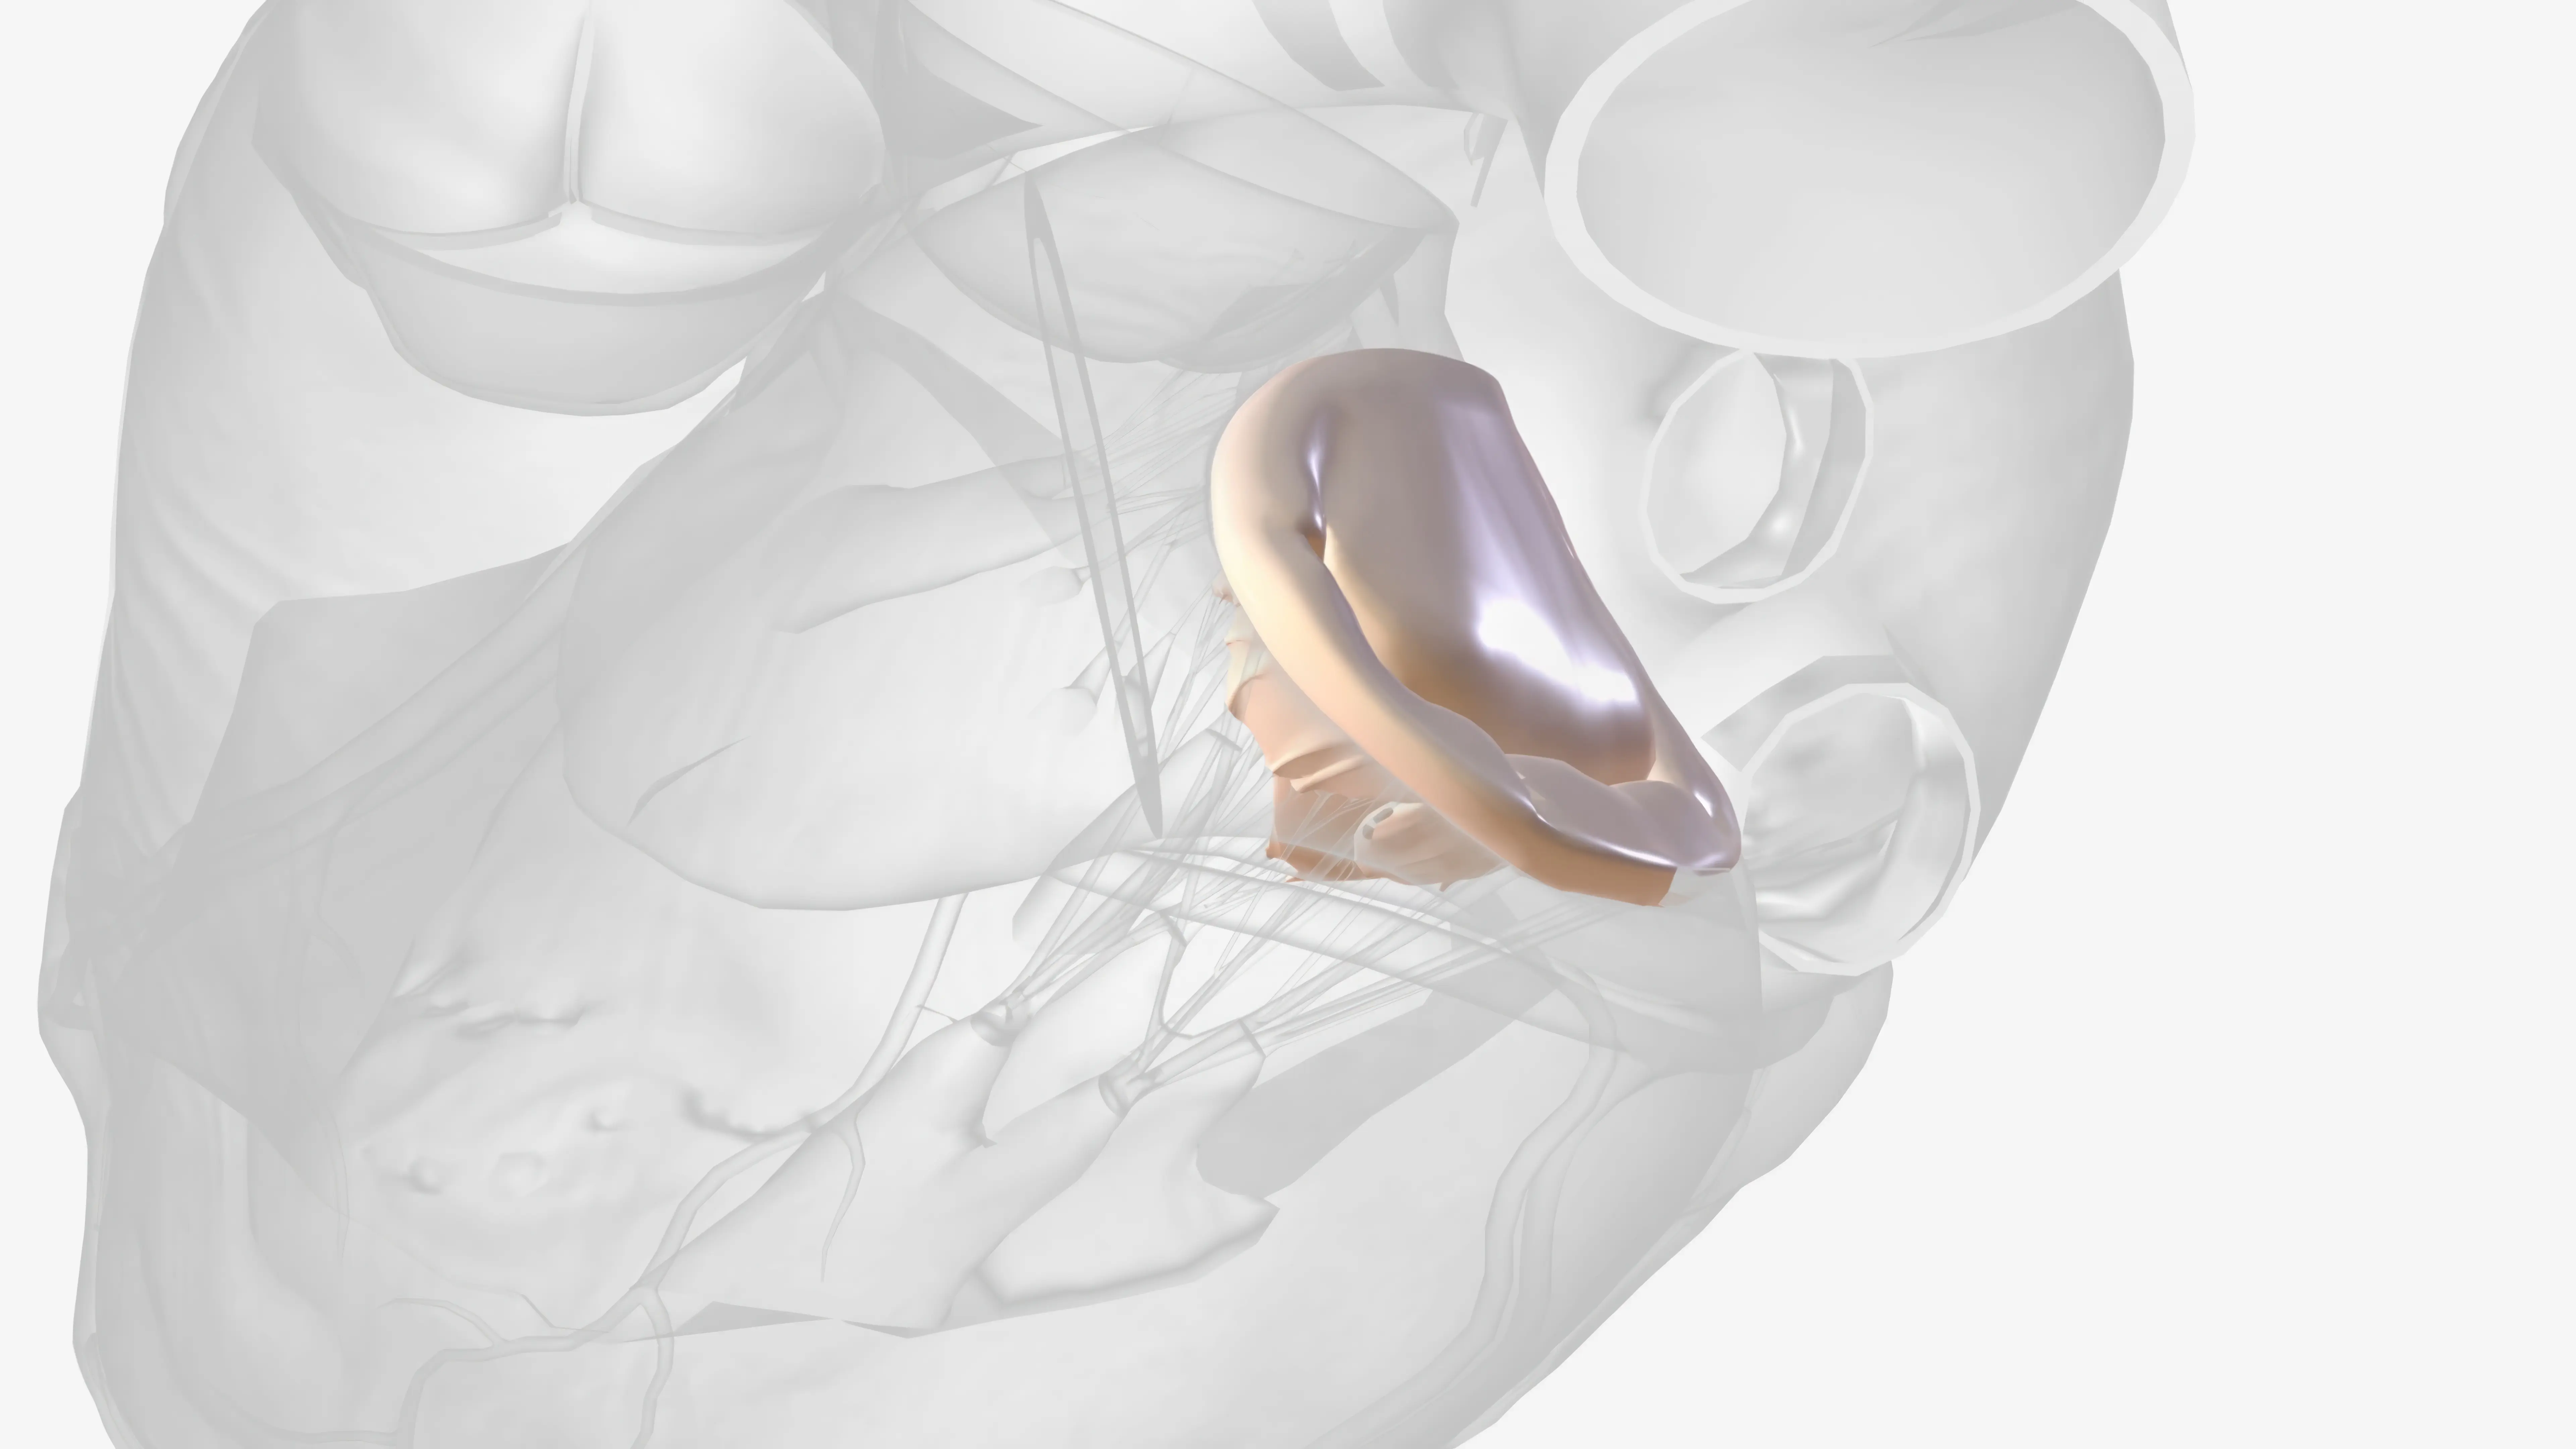

Anüloplasti ile kalp kapak cerrahisinde yenilikler: ring seçimi, transkateter ve invaziv teknikler, izlem ve komplikasyon yönetimini ele alıyoruz.

Kalp Kapak Ameliyatı hakkında türler, hazırlık, cerrahi seçenekler, iyileşme, komplikasyonlar ve yaşam tarzı önerilerini keşfedin.